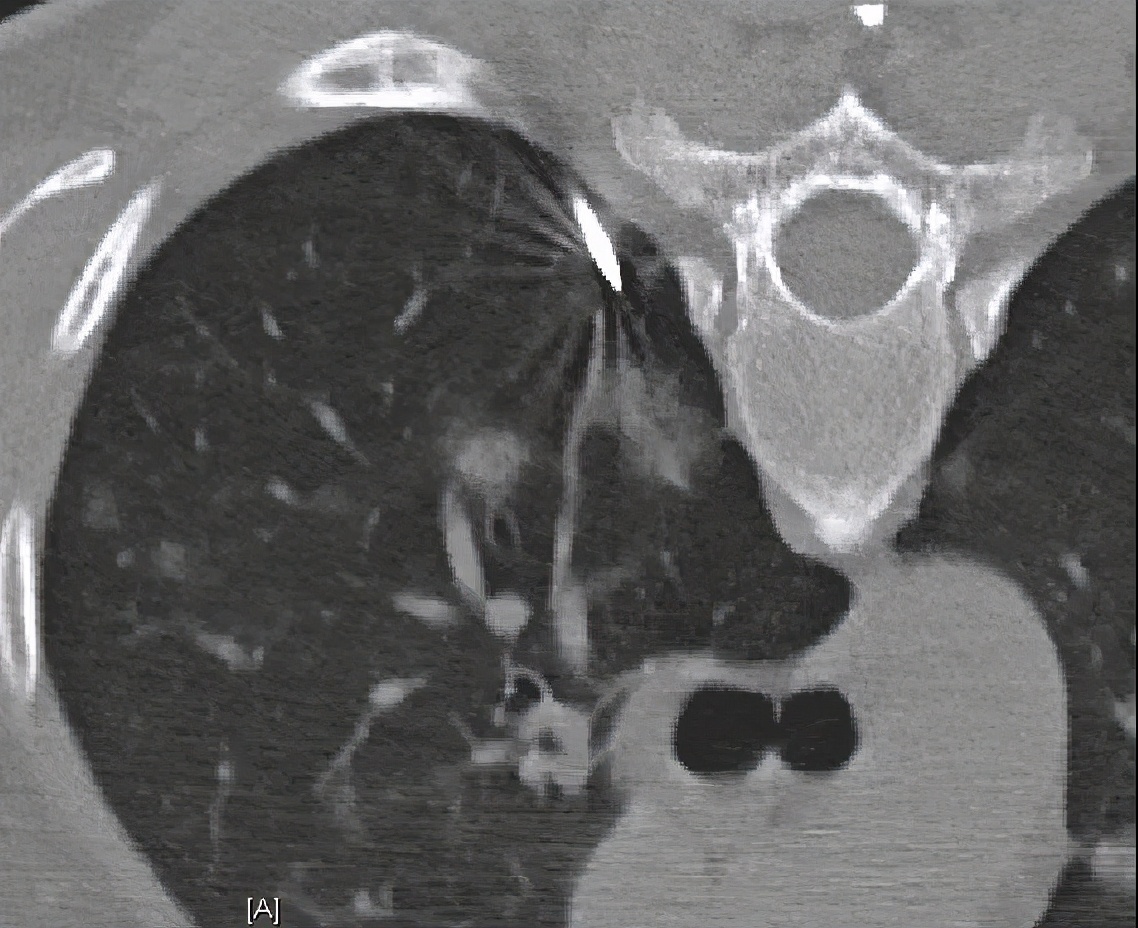

CT引导下肺穿刺活检(2019-05-14)

病理: (肺穿刺)少量支气管壁及肺组织,肺泡间隔明显增宽,可见浆细胞及淋巴细胞浸润,考虑炎症性病变。补充报告:(肺穿刺)特染未提示有血管炎病变。免疫组化:CD31(+),CD34(+)。特殊染色:弹力(-),Masson(-)。

调整治疗方案: 考虑患者机化性肺炎复发,予醋酸泼尼松片15mg qd、硫唑嘌呤片50mg qd治疗,同时辅以兰索拉唑护胃、钙尔奇补钙治疗。